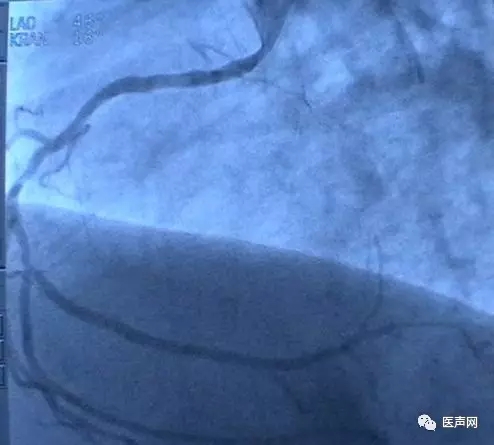

病例1: 冠脉搭桥术后,静脉桥CTO(CABG, VB-CTO)

箭头所示为第3个吻合点

(pre-PCI)

VB-对角支(jump)---LCX(jump)-PDA远端,第一个吻合以下完全阻断。

· 导引导管非常深置(Very very deep seating)(本例GC达CTO 第一吻合口前)(这是Dr. Lauer常用一招)

· 对侧造影

· 硬导丝(走得很远, 达PDA)

· 微导管,OTW 球囊.

当打通后,发生室速,电复律---出现无复流---室速---植入支架(TAXUS Liberte)

当导引导管非常深置(very very deep seating)时,你可以想象支持力有多大,永远不要忘记他做RCA-CTO时导引导管深插到RCA中段的例子。此病例实际上PDA未能开通,在6月28日 Dr. Lauer终于用类似方法打通了PDA。